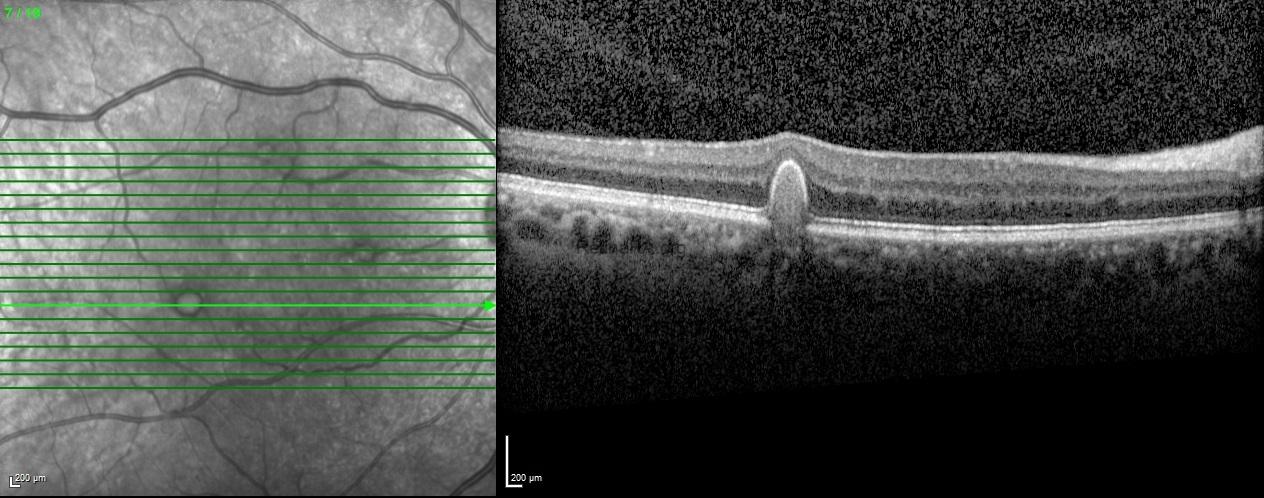

Spectral-domain optical tomography scans passing through the drusen demonstrated the dome-shaped retinal pigment epithelial elevations with variable internal reflectivity of drusen.